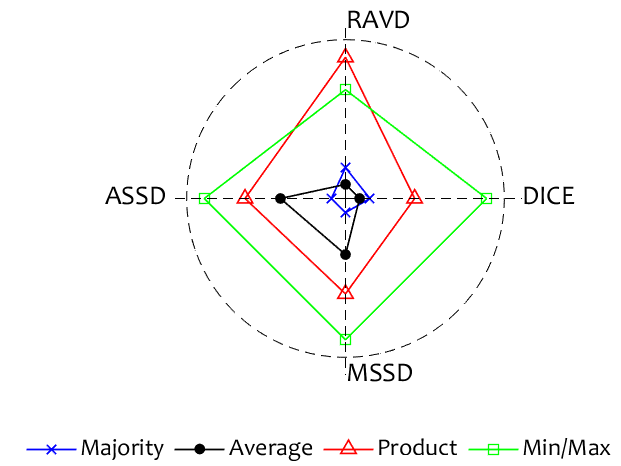

Finally, to be able to recommend one of the ensemble models, we present two glyph plots in Figures 4 and 4. The plots are based on the averaged testing results for each metric. DICE was reversed so that small values are more desirable. The ensemble scores for each metric were scaled between 0.1 and 1 and plotted on the spokes of the glyph plot. An ideal ensemble would occupy a small square in the middle. The larger the surface of the figure presented by the ensemble, the worse the ensemble in comparison with the rest. The Chaos dataset figure elects the Majority Vote ensemble as the best, closely followed by the Average ensemble. On the other hand, the Majority Vote ensemble occupies a large area in the glyph plot in Fig. 4. The Average ensemble is the best for this data set.